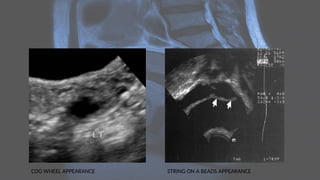

COG WHEEL APPEARANCE STRING ON A BEADS APPEARANCE

COG WHEEL APPEARANCESTRING ON A BEADS APPEARANCE

Radiographic features Ultrasound • Ultrasoundis usually the first imaging requested in a case of lower abdominal pain. • Early findings in PID include : • indistinct uterine margins • echogenic pelvic fat • fallopian tube thickening

• 26.